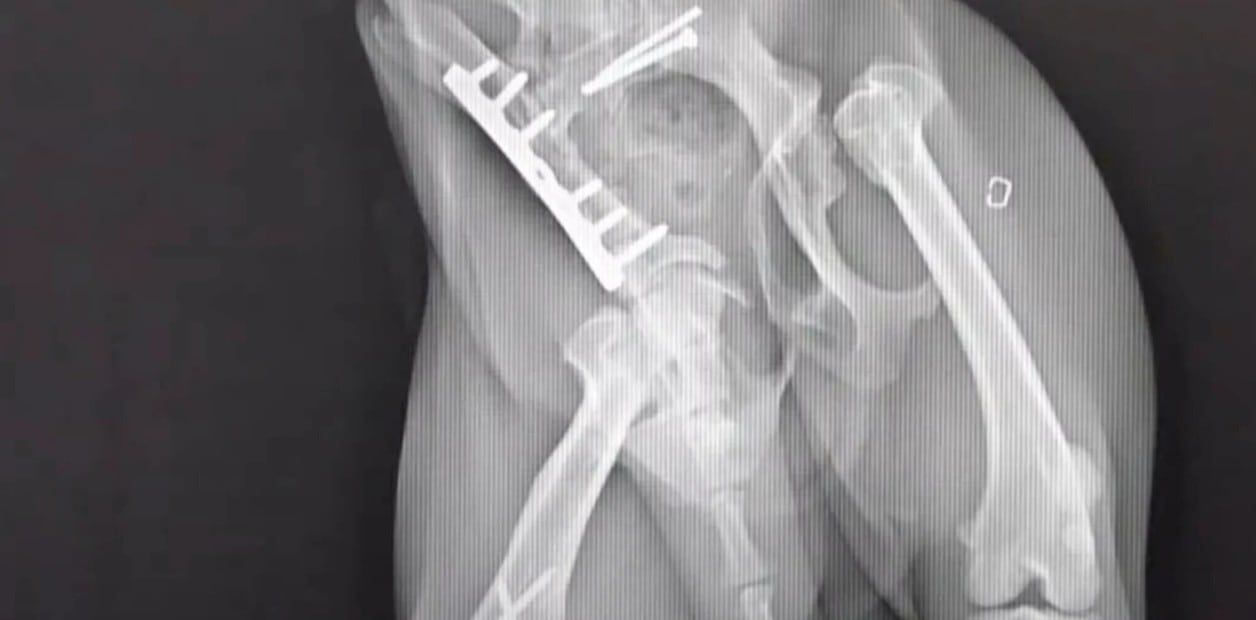

Sorprendidos, los dueños llevaron a Hosun al veterinario de inmediato, donde comenzaron sus tratamientos. Nadie podía creer cómo el animal había conseguido regresar. Algunos vecinos pensaron que se trataba de “un milagro”.

Debido a su fama, un cirujano experto en animales se ofreció a darle una nueva oportunidad a Hosun. Tras una dura y lenta recuperación, la perrita volvió a caminar como si nada hubiera pasado.

Más allá de una ligera discapacidad, Hosun vive como cualquier otro perro. “Ha vivido dos milagros. El primero, cuando volvió a la vida desde la muerte, y el segundo, cuando vive y camina como un perro normal después de graves heridas y una gran operación”.